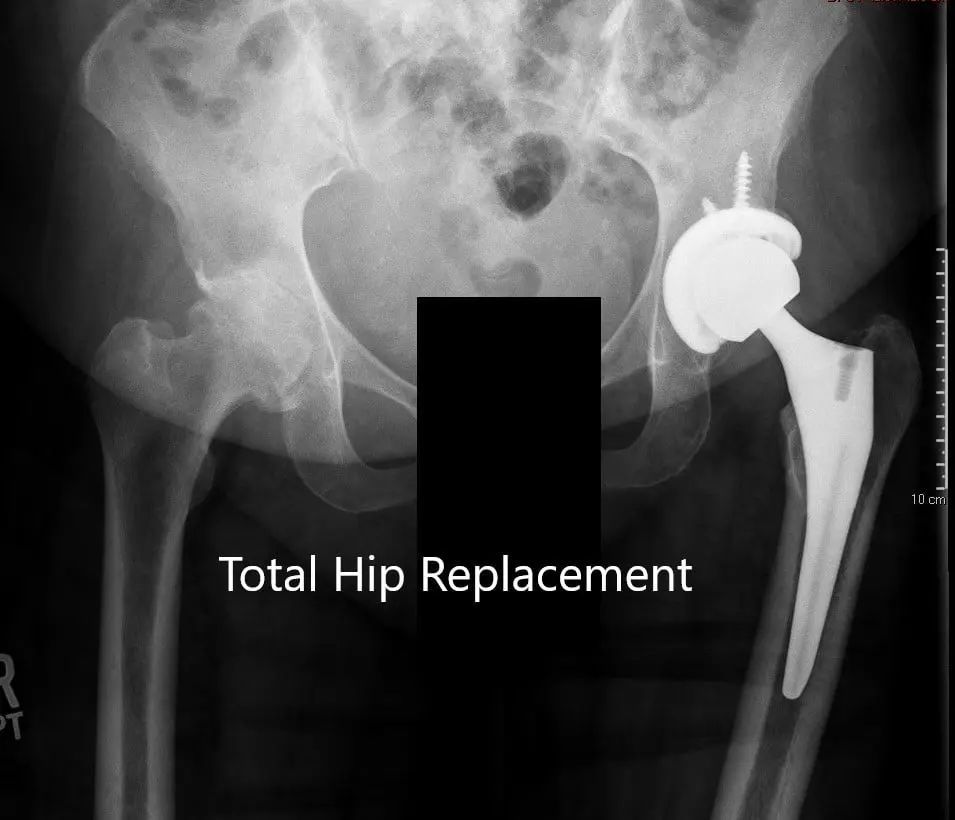

Los estudios de imagen revelaron osteoartritis bilateral de cadera, que era grave en la cadera izquierda con displasia del acetábulo. En vista del dolor de cadera que limita el estilo de vida, le recomendaron una prótesis total de cadera para la izquierda. Se discutieron extensamente con el paciente los riesgos, beneficios y alternativas. El paciente estuvo de acuerdo con el plan.

Radiografía preoperatoria de la cadera izquierda que muestra visión AP y lateral.

OPERACIÓN: Artroplastia total de cadera izquierda usando cabeza femoral cerámica de 36 mm más 5 con un sistema de tallo de cuello de 127 grados tamaño 5 con un agujero de racimo de concha acetabular de 54 mm con inserto de polietileno con dos tornillos.

Radiografía postoperatoria que muestra la vista AP de la pelvis y la vista lateral de la cadera izquierda.